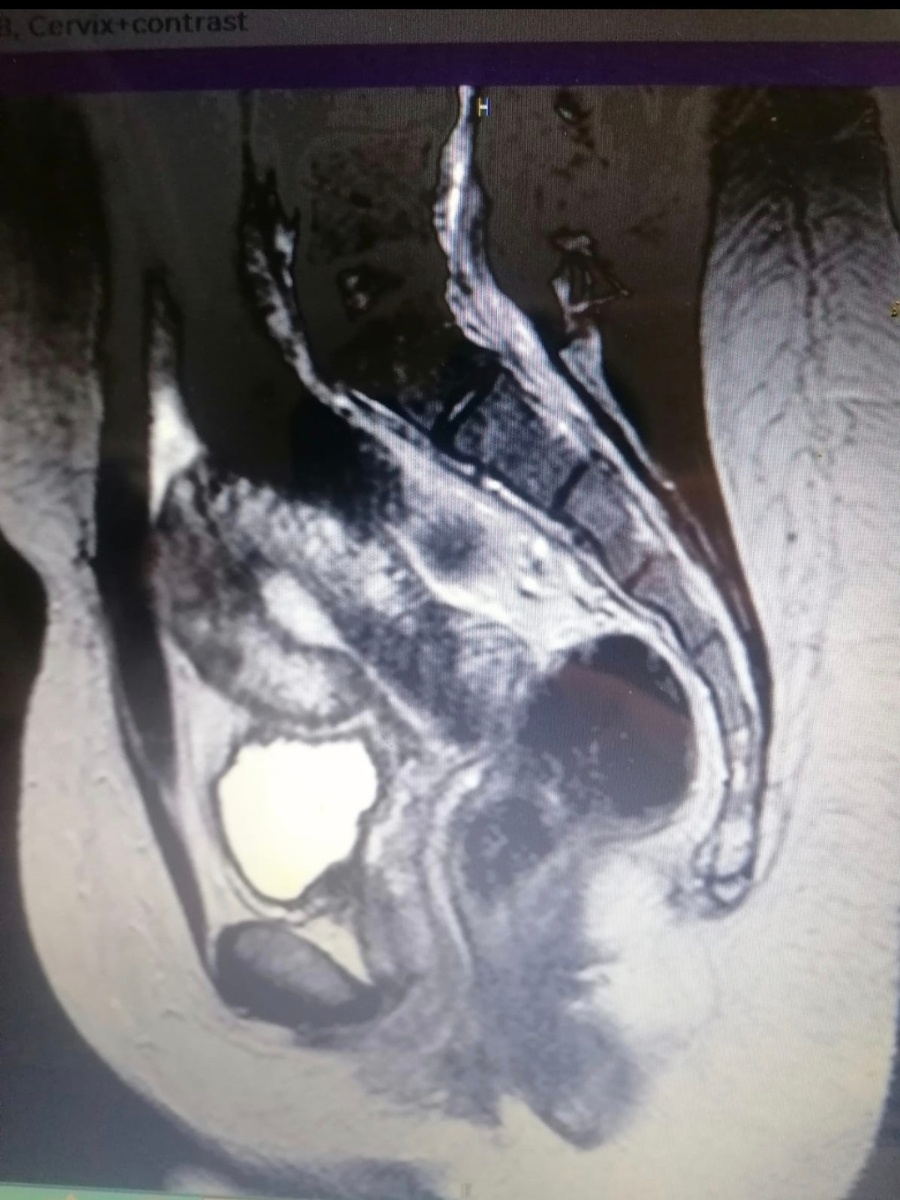

Собственно, шейка матки у Киры выглядела вот так:

Передняя губа шейки матки была длиной всего около 5 мм. С такой длиной шейки не вынашивают.

Истмико-цервикальная недостаточность: шейка просто не выдержит груз беременности. А ребёнка хочется...